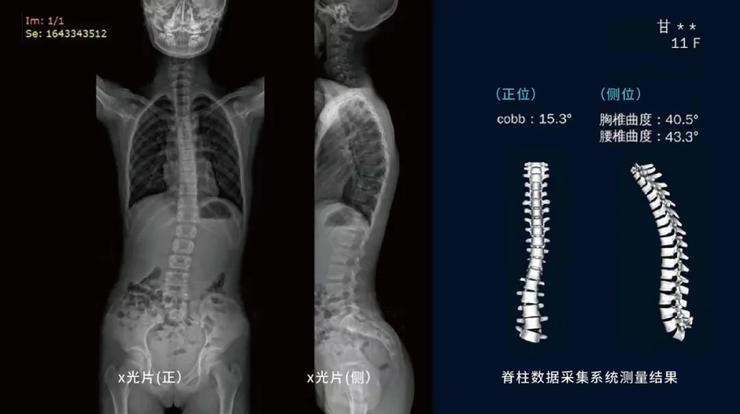

何丹眼下着力的“脊柱侧弯”是一种青少年常见的致残性畸形,它包括冠状位、矢状位和轴位的脊柱锥体排列异常,发病存在隐蔽性。

“目前医院常用X光射线检测脊柱侧弯,这是目前医学上最准确的检测方式,但辐射面积相对较大,容易对人的血液系统和生殖系统等造成不可逆的损害。尤其是那些已经发现侧弯或存在侧弯倾向的孩子,为了更好地治疗矫正,他们需要在18岁前持续随访,不停地去拍X光。”何丹解释道。“这样的诊治方式对于孩子而言危害相当大。我曾读过一篇相关研究,数据显示:当脊柱侧弯患者持续随访二十年,他的癌症发病率骤升,达到了普通人的500%。”

据何丹表示,该系统是目前全球首款无辐射直接测量脊柱Cobb角和ATR角的脊柱健康检查设备,且有人工智能技术作为支持。

在上海瑞金医院放射科完成的与国际最先进的脊柱侧弯X线影像设备EOS对比的双盲临床验证试验中,初步测量结果显示,该设备在脊柱侧弯检测方面与X光有显著一致性。